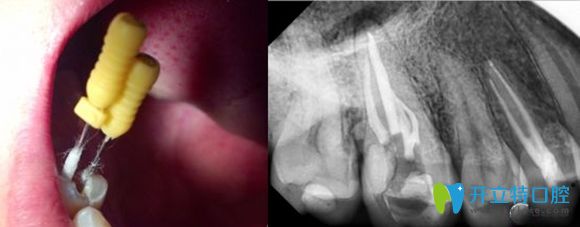

根管治療過程圖解

根管治療就是牙醫(yī)利用專用的器械,去除牙齒內(nèi)部感染的牙髓以及感染的牙本質(zhì),還有毒性分解產(chǎn)物,并進行適當?shù)南荆缓笤龠M行嚴密充填根管,防止發(fā)生根尖周病變,或者是促進根尖周病變愈合的一種治療方法。

牙齒根管治療科普圖

牙齒根管治療過程中圖片

根管治療后的X線片影像圖